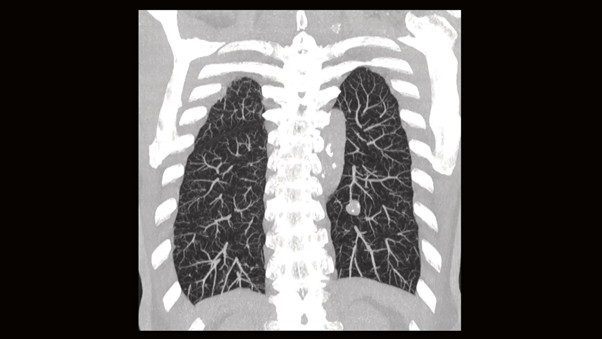

Снимок легких на КТ Siemens SOMATOM go.Now.

Изначально компьютерный томограф получает только аксиальные срезы — это поперечные «ломтики» тела, как если бы мы смотрели на пациента со стороны ног. Современные мощные станции мгновенно выполняют мультипланарную реконструкцию (MPR). Это значит, что программа берет стопку поперечных срезов и строит из них изображения в других плоскостях:

- фронтальная (корональная) — вид спереди;

- сагиттальная — вид сбоку;

- 3D-модель — объемное изображение костей и сосудов.

Таким образом, из одного сканирования врач получает полную трехмерную картину состояния пациента.